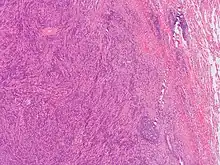

This image was originally posted to Flickr by Pulmonary Pathology at https://flickr.com/photos/30950973@N03/5601450952 (archive). It was reviewed on 3 October 2019 by FlickreviewR 2 and was confirmed to be licensed under the terms of the cc-by-sa-2.0.

General image of plasma cell granuloma that was classified in a broader category of inflammatory pseudotumor. Original author of image was: Yale Rosen from USA[10]

PCGs were first discovered and described in 1973 by Bahadori and Liebow.[1] PCGs are characterized by the proliferation and infiltration of different inflammatory cells with the main cell observed in highest concentrations being plasma cells.[1][2] More specifically, PCGs are a type of mass-forming lesion arising from the accumulation of polyclonal plasma cells surrounded in a swirling storiform orientation of fibrosis and spindle cell proliferation.[3][4] It has been noted that these granulomas have the propensity to manifest on any organ or soft tissue.[3] Plasma cell granulomas are generally found to be benign, but in some cases, the granulomas have the ability to initiate malignancy and become symptomatic regardless of location or size.[3] Common sites of plasma cell granulomas are in the oral gingiva, lungs, vagina, larynx, orbit, spinal cord meninges, breast, pelvic soft tissue, bladder, mesentery, retroperitoneum, kidney, lymph nodes, spleen, pancreas, liver, stomach, heart, thyroid, and trachea.[1][4][5][6] Microscopically, plasma cell granulomas, demonstrate a lesional pattern of inflammatory pseudotumor.[1] The term inflammatory pseudotumor has previously been used to classify plasma cell granulomas. However, this term has become more uncommon in recent years due to its lack of specificity.[3] Today, scientist use more up to date diagnostic and medical terminology to avoid classifying lesions in the same group that are likely to have different etiologies.[3] Other names associated with plasma cell granulomas are inflammatory myofibroblastic tumor, inflammatory myofibrohistiocytic tumor, benign myofibroblastoma, pseudosarcoma, fibrous histocytoma, fibroxanthoma, xanthomatous pseudotumor, xanthogranuloma, myxoid hamartoma, and lymphoid hamartoma.[1][2][4][7][8][9]

Since plasma cell granulomas have the ability to occur at any site, even though they are uncommon, it should be included in differential diagnostics in regard to plasma cell neoplasms.[3] With granulomas that arise in the mouth, PCGs are commonly misclassified considering the malignancy of the disease due to its aggressive behavior and clinical presentation.[4] Plasma cell granulomas located in the oral cavity have been identified with disruption and damage of surrounding tissues.[4] In comparison, PCGs manifesting in other internal organs are usually secondary findings on radiographic images.[4] Occasionally, plasma cell granulomas are misdiagnosed as malignant lymphoma or malignant plasmacytoma during initial examination due to radiological evidence of its ability to erode and infiltrate bone.[4] Typically, under microscopic analysis, a plasma cell granuloma will display a dense population of morphologically similar plasma cells sporadically mixed together with other inflammatory lymphocytes seen in a storiform orientation of fibrotic connective tissue.[3][4] To avoid the misdiagnosis of a PCG as a plasmacytoma, it should be noted PCGs are formed from typical plasma cells while plasmacytomas consist of both atypical and typical plasma cells.[4] It is imperative that such differentiation between plasma cell granuloma and plasmacytomas are completed prior to informing the patient undergoing clinical examination.[4] The importance of an accurate diagnosis between the two is due to the different prognosis and progression of the mass-forming lesions.[4] While plasma cell granulomas are often found to be benign, plasmacytomas have been associated with a more aggressive and invasive behavior in which they have the ability to transform or evolve into multiple myeloma.[4] One of the most reliable distinguishing factors from plasmacytomas and plasma cell granulomas, is the polyclonality of the plasma cells involved with plasma cell granulomas.[3] PCGs that manifest in the mouth, specifically the gingiva, have been seen to exhibit similar physical characteristics of other conditions such as epulis, fibroma, pyogenic granuloma, and peripheral giant cell granuloma.[4] Histopathological analysis of plasma cell granulomas have been found to be the most precise confirmative diagnosis to distinguish PCGs from other lesional tumors of plasma cell origins.[4]

Analyzing the changes that arise in the tissue associated with the mass-forming lesion has been found to be the most accurate and precise method for confirming the diagnosis of plasma cell granulomas. This can be achieved by taking excision biopsies of the unknown mass for examination.[4] Typically, plasma cell granulomas appear microscopically as a lesional mass consisting of an abundance of plasma cells intermingled among different inflammatory cells set in fibrous connective tissue displayed in a spiral appearance.[3][4]  Depending on the location of the plasma cell granuloma, vasculitis can be present but is not considered a confirmatory factor for diagnosis.[3] Kappa/lambda in-situ hybridization is another diagnostic test that needs to be done when trying to characterize the lesion for further confirmation.[3] Common results associated with kappa/lambda in-situ hybridization studies of PCGs are an abundant population of CD138 positive polyclonal plasma cells.[3] If instead, results show monoclonality of plasma cells it is indicative of plasmacytoma.[3]